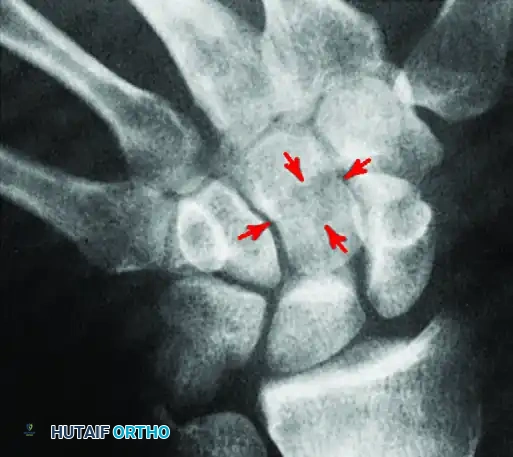

Specialized projections, such as the carpal tunnel view, are essential for identifying specific osseous pathologies, including avulsion fractures of the hamate hook or trapezium, which may present as vague volar wrist pain. Furthermore, occult fractures of the carpal bones require careful radiographic scrutiny.

As demonstrated above, a standard PA view of the capitate may show no definite abnormality. However, an angled view can reveal a cystic defect with an associated fracture in the capitate waist. Recognizing these subtle osseous lesions preoperatively allows the surgeon to plan for concurrent arthroscopic debridement or percutaneous fixation.